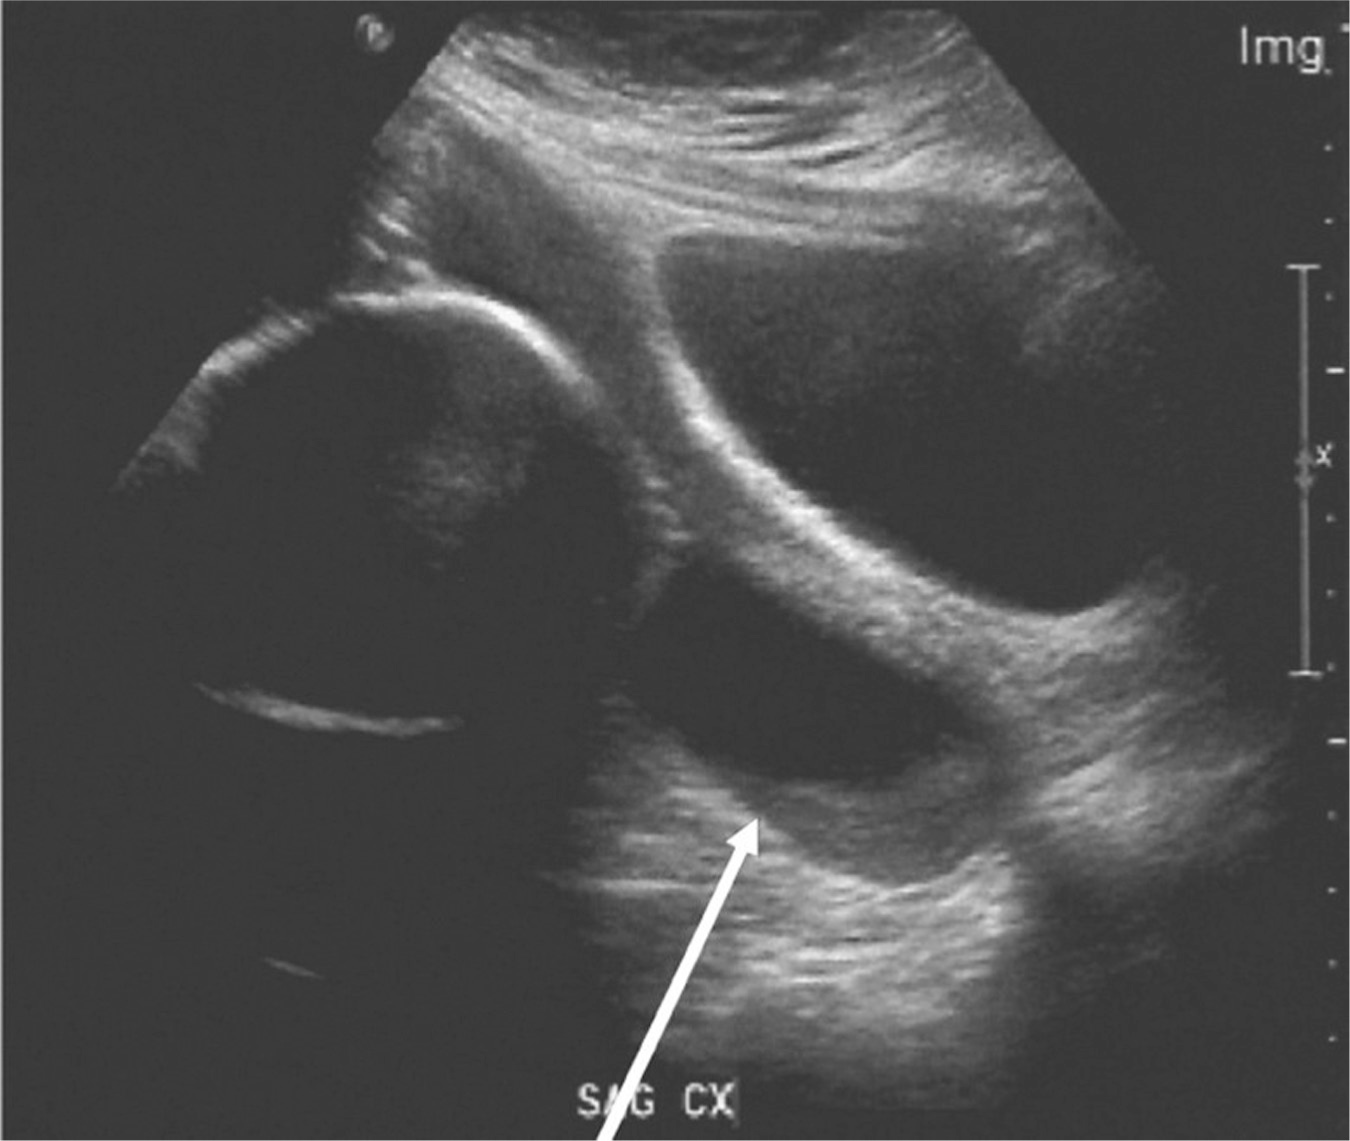

From www.trialexhibitsinc.com

Ultrasound of a Short Cervix TrialQuest Inc. Cervical Shortening Definition Identifying these women at risk allows clinicians the opportunity to. Essentially, effacement refers to the thinning of your cervix, the low, narrow end of the uterus that connects to. Short cervical length (cl) found on morphological scan is associated with an elevated risk of spontaneous ptb. For about 1 percent of expectant mothers who experience preterm labor, the cause is. Cervical Shortening Definition.